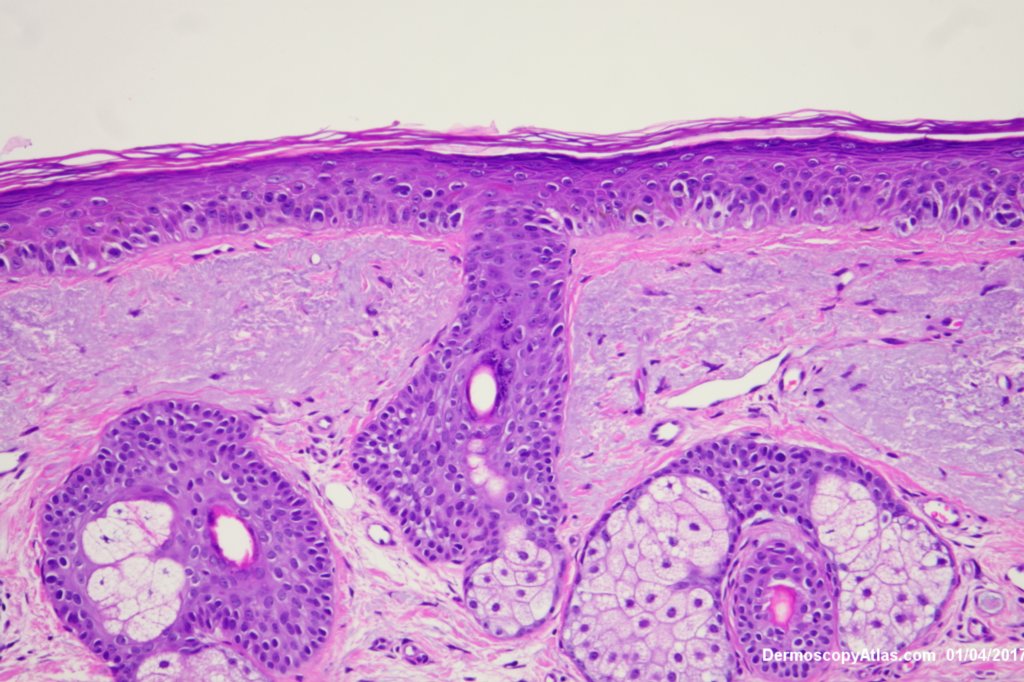

Description: Lentiginous proliferation of atypical melanocytes

The Dermatoscopy shows partial grey circles and the histology shows a lentiginous proliferation of atypical melanocytes involving the hair follicles.